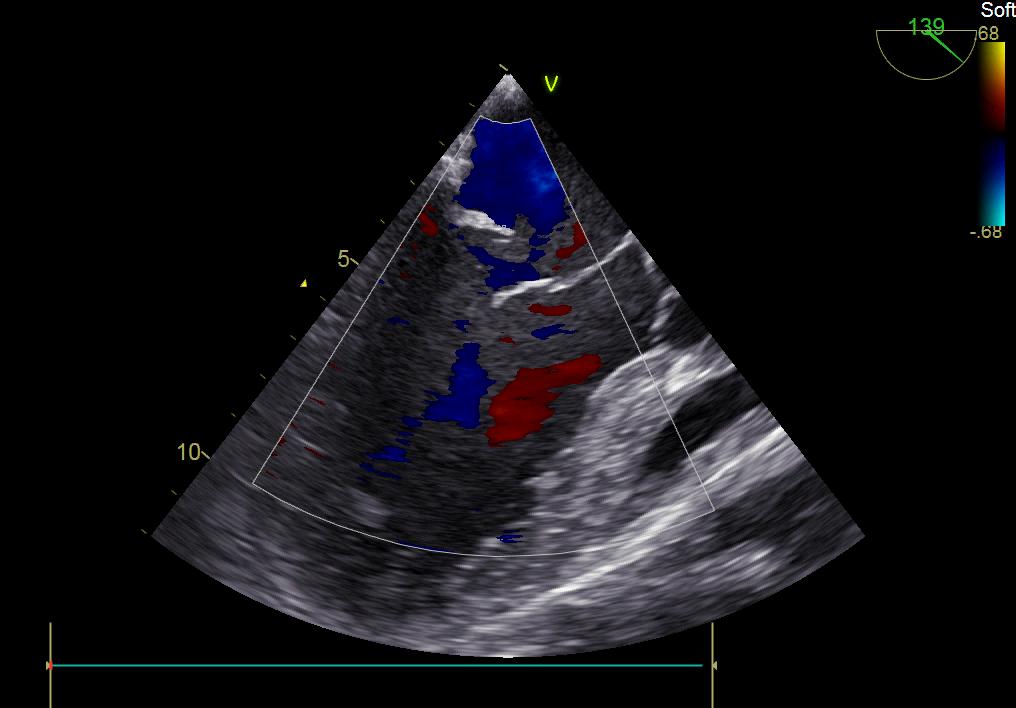

患者何某,42歲男性,因心功能不全入住我院心胸外科,心臟彩超提示二尖瓣后葉脫垂伴有重度返流及心臟擴(kuò)大,在迅速糾正心衰后,手術(shù)便提上日程,心胸外科廖金文主任多次組織全科及兄弟科室討論,在二尖瓣置換及成形術(shù)上,最終決定采取二尖瓣成形術(shù)。為保證手術(shù)安全,討論圍手術(shù)期各個(gè)細(xì)節(jié),所謂細(xì)節(jié)決定成敗,因?yàn)樾g(shù)前的細(xì)致全面,加上術(shù)中的一絲不茍及術(shù)后的精細(xì)化管理,患者術(shù)后恢復(fù)順利,健康出院,復(fù)查心臟彩超未見(jiàn)二尖瓣返流。

術(shù)前彩超